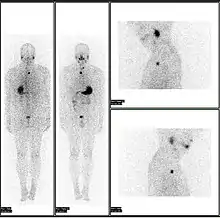

A nuclear medicine whole body bone scan. The nuclear medicine whole body bone scan is generally used in evaluations of various bone-related pathology, such as for bone pain, stress fracture, nonmalignant bone lesions, bone infections, or the spread of cancer to the bone.